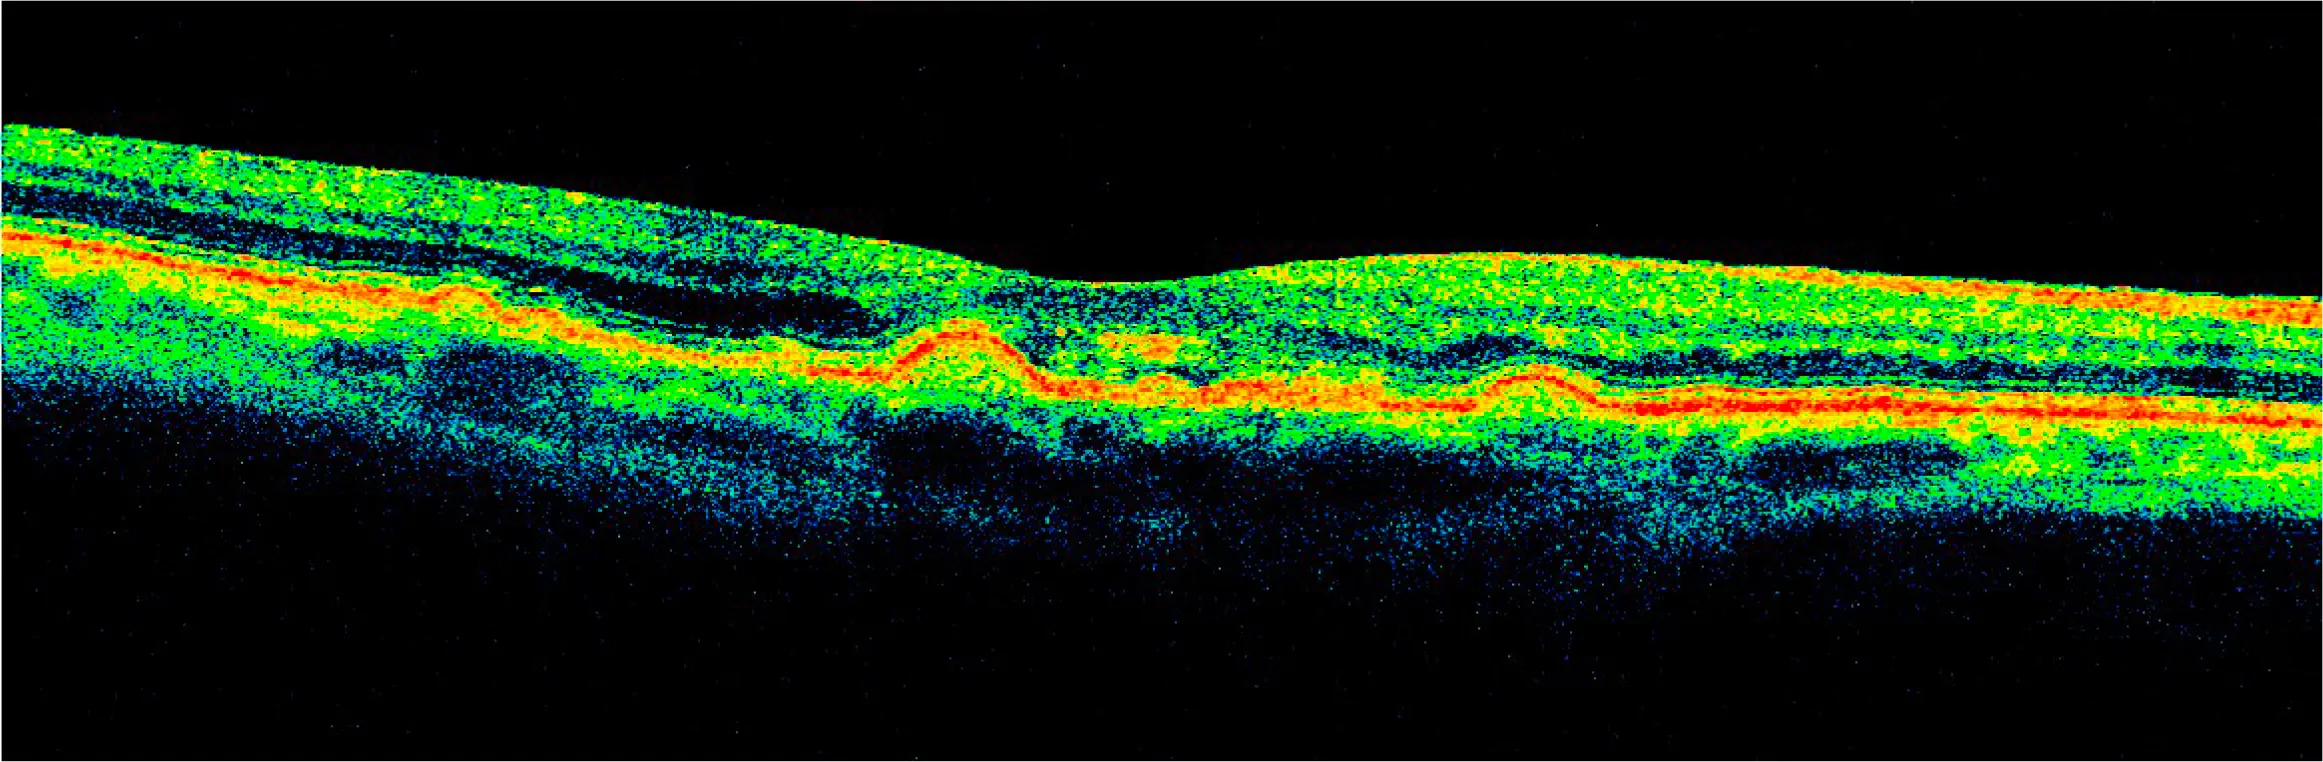

At her 6-month follow-up, her drusen were decreased by about 70%.

It inspired me to use AI to turn the OCT scans into a video to help visualize the healing process...

After years of deterioration on AREDS2 and other more conventional nutritional supplements, drusen largely resorbed in 15 months on a higher priced broad spectrum botanical/nutritional regimen, restoring 20/20 visual acuity in each eye as well as distortion-free Amsler Grids.